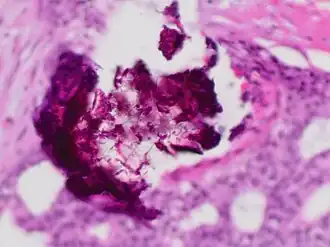

Dystrophic calcification

Dystrophic calcification (DC) is the calcification occurring in degenerated or necrotic tissue, as in hyalinized scars, degenerated foci in leiomyomas, and caseous nodules. This occurs as a reaction to tissue damage,[1] including as a consequence of medical device implantation. Dystrophic calcification can occur even if the amount of calcium in the blood is not elevated, in contrast to metastatic calcification, which is a consequence of a systemic mineral imbalance, including hypercalcemia and/or hyperphosphatemia, that leads to calcium deposition in healthy tissues.[2] In dystrophic calcification, basophilic calcium salt deposits aggregate, first in the mitochondria, then progressively throughout the cell. These calcifications are an indication of previous microscopic cell injury, occurring in areas of cell necrosis when activated phosphatases bind calcium ions to phospholipids in the membrane.